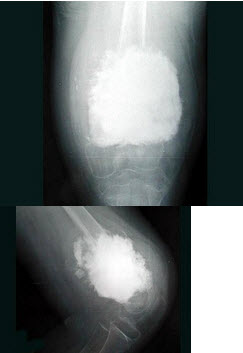

7、单项选择题

女,10岁,左大腿疼痛,夜间加重,肿胀明显,结合图像,最可能的诊断是()

A.成骨性骨转移

B.化脓性骨髓炎

C.骨肉瘤

D.骨化性肌炎

E.以上都不正确